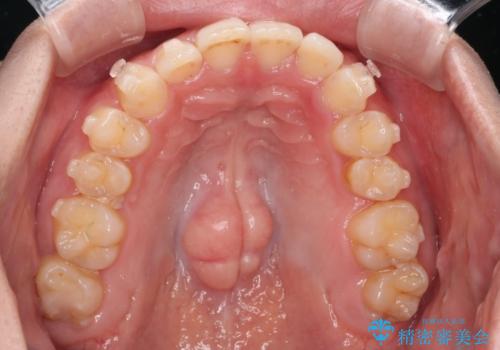

- 下の歯のがたつきを主訴に来院されました。

下の歯のがたつきと右の奥歯の噛みあわせ改善するために治療計画を立てることにしました。

右側臼歯部の咬合改善のために、臼歯部のみ部分的なワイヤー矯正を行い、咬合改善がみられてからインビザラインにて全体的な矯正を行なっていく治療計画を立てました。